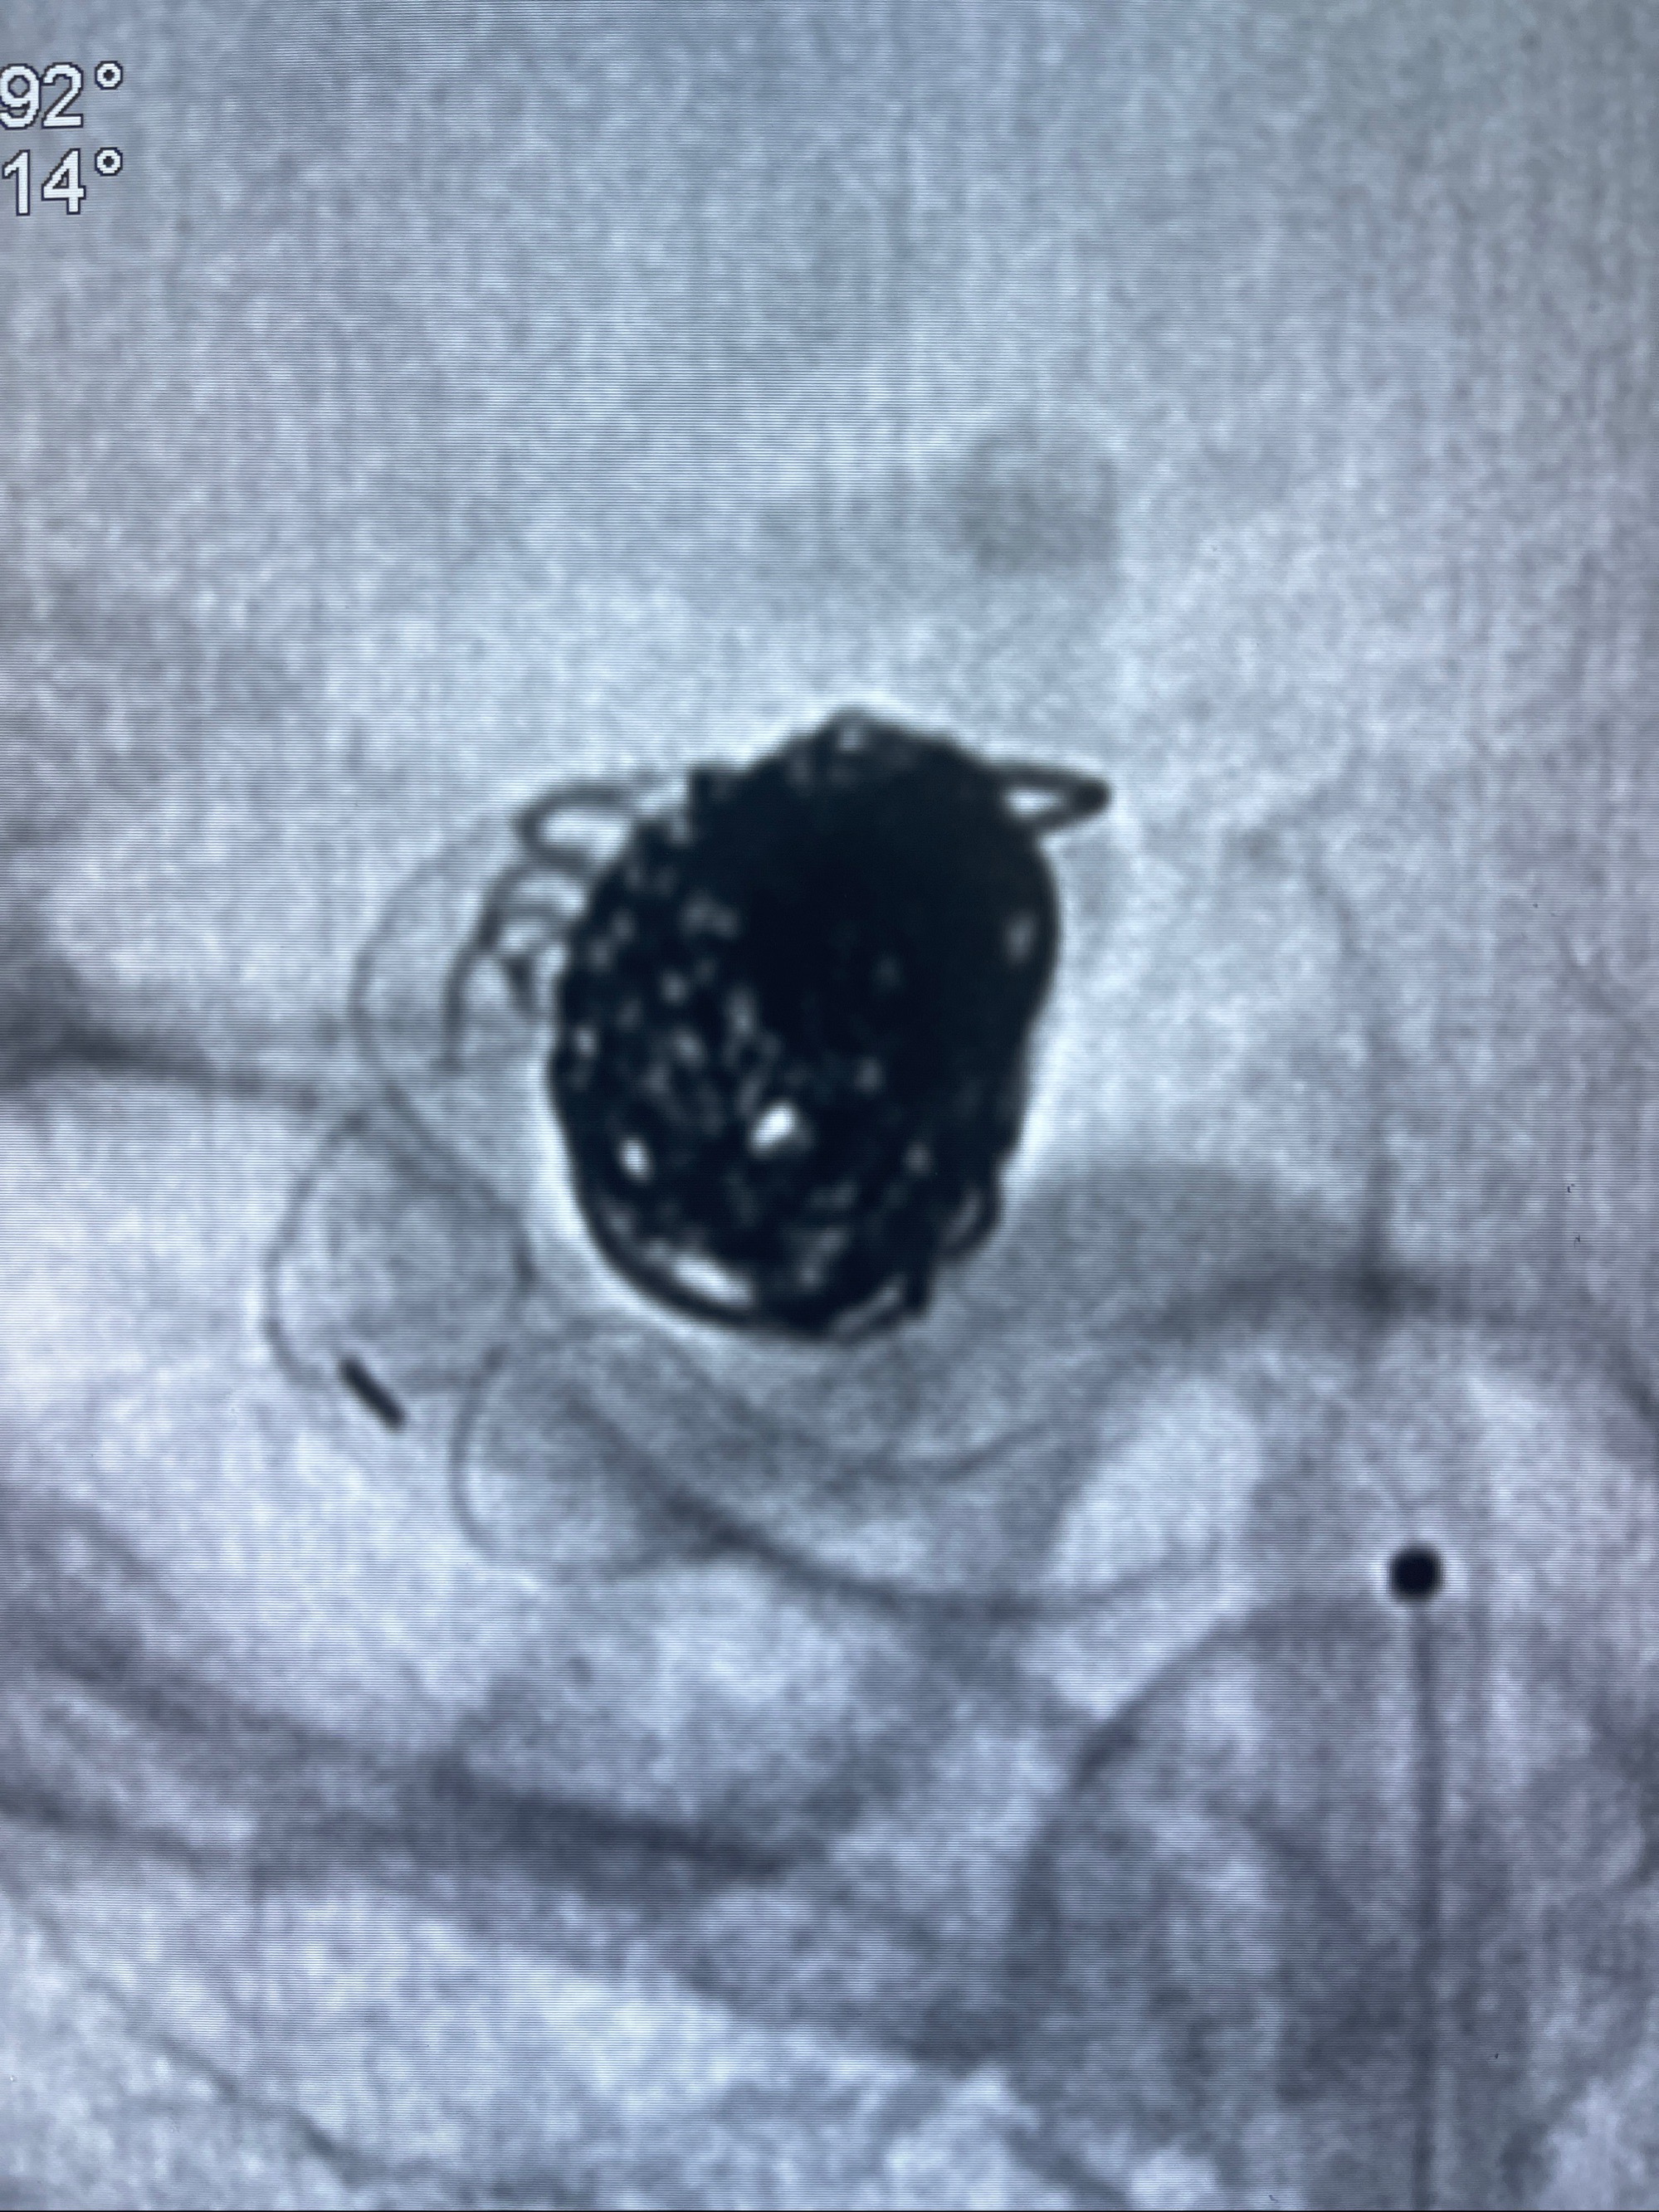

- Tubridge 4.0-20mm密网支架

- 加奇微弹簧圈:7*30/6*20/5*20/2*8

术后3D显示支架贴壁佳